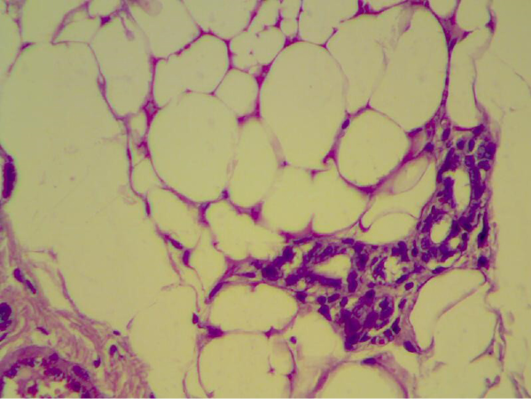

Mammary gland section shows mild inflammatory cell with normal looking adipose tissue. (H&E 200 X) (H&E 400 X)